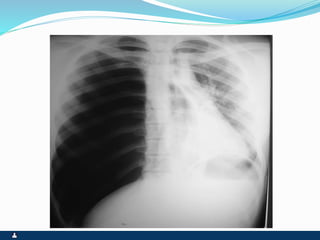

ATELECTASIA

ATELECTASIA ENFISEMA LOCALIZADO

 OBSTRUÇÃO BRONQUICA

COMPLETA

 RETRAÇÃO TORÁCICA OU

INTERCOSTAL

 DESVIO HOMOLATERAL DO

MEDIASTINO ( TRAQUÉIA)

 EXPANSIBILIDADE REDUZIDA

 FTV AUSENTE

 MACICEZ LOCALIZADA

 MV AUSENTE

 RONCOS OU SIBILOS

LOCALIZADOS

 ATRITO PLEURAL EVENTUAL